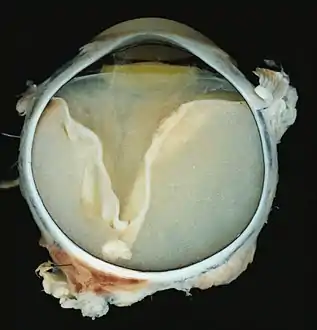

A case of Coats' disease, showing total retinal detachment with subretinal exudate containing cholesterol crystals and a fibrous nodule in the posterior pole

A case of Coats' disease, showing total exudative retinal detachment, and subretinal exudate containing cholesterol crystals (H&E)

Grossly, retinal detachment and yellowish subretinal exudate containing cholesterol crystals are commonly seen. Microscopically, the wall of retinal vessels may be thickened in some cases, while in other cases the wall may be thinned with irregular dilatation of the lumen.[10] The subretinal exudate consists of cholesterol crystals, macrophages laden with cholesterol and pigment, erythrocytes, and hemosiderin.[11] A granulomatous reaction, induced by the exudate, may be seen with the retina.[12] Portions of the retina may develop gliosis as a response to injury.